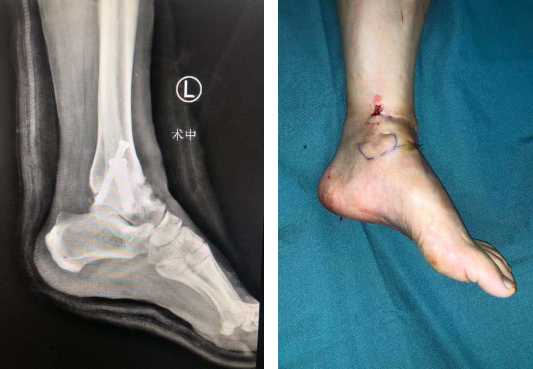

术中

术后X线(左图)术后(右图)

石荣剑副院长周吉医生手术团队为患者进行了手术。术中,医生操作关节镜进入踝关节腔内探查,刨削器清理肉芽组织、充血滑膜组织,清理踝关节各软骨面,术中取出两块增生骨赘游离体,这是导致患者关节疼痛的一个因素;随后,在踝关节间隙填充人工异体骨,在机器人精准定位下分别从胫骨近端、腓骨近端交叉钉入3枚克氏针作为导针,沿导针钉入空心螺钉3枚,C型臂透视见踝关节融合位置良好,内固定在位。手术顺利结束。